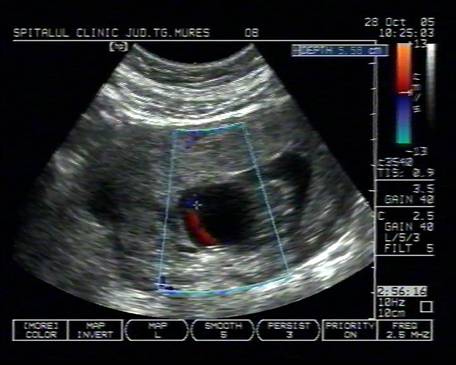

Fig. nr.125 Omfalocel la o sarcina de 12 saptamani ( zona anecogena marcata cu caliper )

Fig. nr.126 Acelasi fat ca in figura precedenta, sectiune transversala abdominala, cu ecou Doppler la periferia omfalocelului